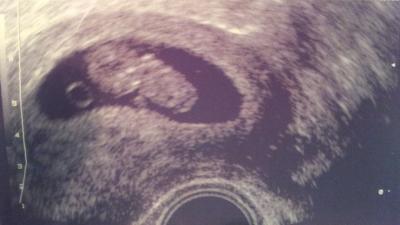

Hallo zusammen, ich hatte gestern auch einen FA-Termin und es sieht soweit alles gut aus. Das Kleine hatte eine SSL von 27. War damit 1-2 Tage zurück. Was mache jetzt schon wieder verunsichert. Aber der FA meinte, dass dies durch Messfehler schnell passieren kann. Naja, letztlich hilft ja leider sowieso nur, weiter abzuwarten. Ich darf auch in 2 Wochen dann in der 12. SSW nochmal wieder kommen und hoffe, dass dann alles in Ordnung ist weiterhin und ich etwas beruhigter an die Sache rangehen kann. Liebe Grüße Ella

Bild zu FA-Termin gestern - Forum für Mai - Mamis